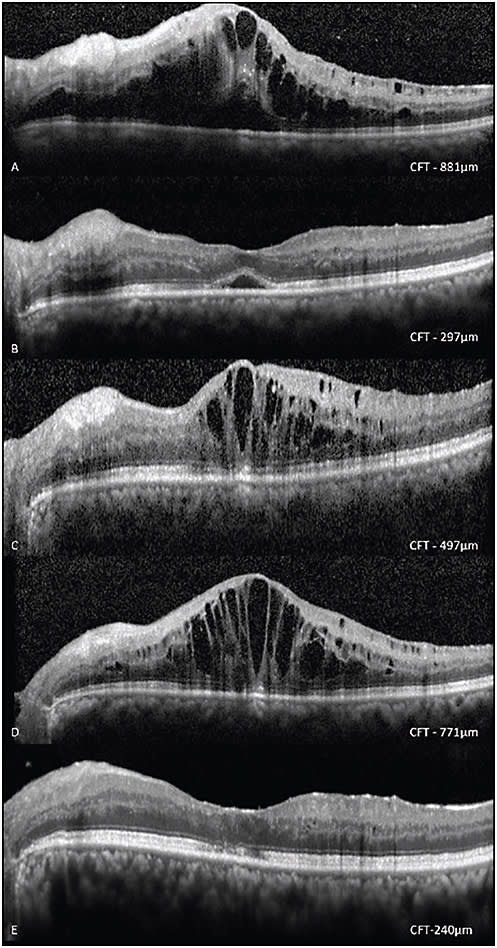

Figure 1. A 60-year-old male patient with CRVO in the left eye (A), who previously received three injections of IVB, showed initial response (B) but later demonstrated recurrence (C) and worsening after a third dose of IVB (D) Subsequently, cytokine levels were analyzed (VEGF, IL-6, IL-8 levels of 29.94, 1.31, 82.12 pg/mL, respectively); correspondingly, IVTA was administered with complete resolution of ME and no recurrenceatn two consecutive monthly follow-ups. CFT – Central foveal thickness, IVB – Intravitreal bevacizumab, IVTA – Intravitreal triamcinolone acetonide.